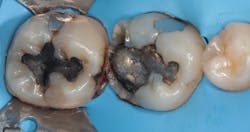

A patient presents with large cavities that have been previously addressed with amalgam. After removing the amalgam and achieving isolation, an alginate is used to take an impression (figures 1–4). A working model is made by first placing light silicone material in the impression and then supporting it with putty to provide rigidity (figures 5a-c). A second working model is made to allow for “flexion” of the dies. This allows separation of the individual teeth and preparations for adjusting proximal margins and interproximal contacts of the restoration as needed.